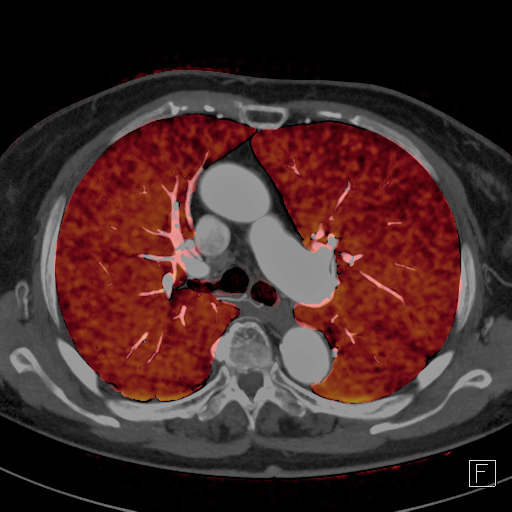

脱水や長時間同じ姿勢を取ることなどで脚の静脈の流れが悪くなり、血栓ができることがあります。その血栓が肺に運ばれて肺動脈を詰まらせてしまうのが肺血栓塞栓症です。CTを用いることで肺動脈内の血栓を造影欠損像として直接描出できます。さらに、デュアルエナジー撮影法を利用すると肺血流の機能情報を可視化することができます。

デュアルエナジーイメージングによる肺灌流評価CT(治療前と抗凝固薬服用後)